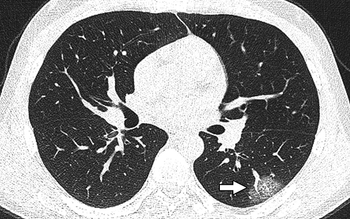

Scans reveal differences in lesion locations, mucoid impaction, and pleural effusion.

Patients who test negative with RT-PCR show lower levels of pulmonary consolidation on chest CT, indicating earlier disease.